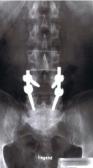

Ich weiß wie das ist aber trotzdem habe ich vom Jobcenter bis jetzt, obwohl ärztliches Attest und Krankengeschichte dem Amt vorliegen ( 4x Krankenhaus mit 2 OP's innerhalb eines Jahres mit Ergebniss:siehe Bild ),nur nur Arbeiten für 1€ angeboten bekommen habe die für mich körperlich nicht zumutbar waren weil man nur eine Nummer in der Menge ist.